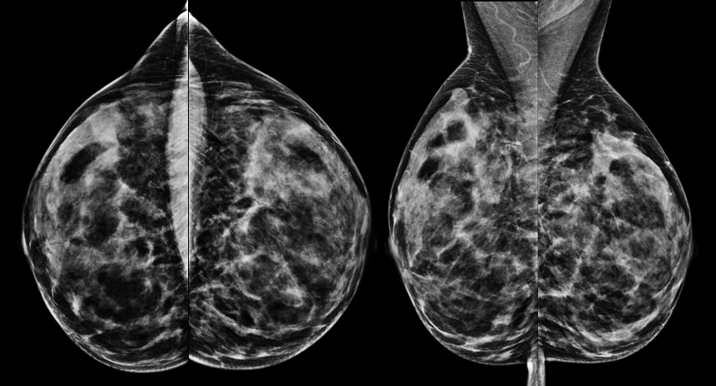

Mammographie einer 52jährigen Patientin zur Brustkrebsfrüherkennung

Die Mammographie ist eine Röntgenaufnahme der Brust, mit der gutartige und bösartige Veränderungen dargestellt werden können. Diese Untersuchung ist die einzige anerkannte Untersuchung zur Brustkrebsfrüherkennung und die einzige Methode, mit der auch kleine Verkalkungen in der Brust zuverlässig erkannt werden können. Im Rahmen des Mammographie-Screenings werden alle Frauen im Alter von 50-69 Jahren alle 2 Jahre zur Mammographie eingeladen. In diesem Alter tritt Brustkrebs am häufigsten auf, daher ist eine Mammographie hier in jedem Fall empfehlenswert. Darüber hinaus gibt es Hinweise darauf, dass auch jüngere Frauen ab dem 40. Lebensjahr und ältere Frauen (70 Jahre und älter) in bestimmten Fällen von einer Mammographie profitieren. Wenn bei der jährlichen Tastuntersuchung durch den Frauenarzt oder bei der Brustselbstuntersuchung (Tasten) auffällige Befunde erhoben werden, eine verdächtige Flüssigkeitsabsonderung aus der Brustwarze (blutig oder klar) besteht oder eine neu aufgetretene Hauteinziehung oder Rötung auftritt, ist die Mammographie bei Frauen ab 40 Jahren die erste Methode, die zur Abklärung dieser Befunde eingesetzt werden sollte.

Bei der Mammographie entsteht das Bild entweder durch Belichtung eines Röntgenfilms (Film-Folien-Mammographie) oder mit Hilfe eines digitalen Bilddetektors (digitale Mammographie). Beide Systeme erreichen eine ähnliche Bildqualität. Studien haben gezeigt, dass bestimmte Veränderungen (Mikrokalk) etwas besser mit der digitalen Technik dargestellt werden können. In der Universitätsklinik Tübingen sind zwei digitale Mammographie-Systeme installiert, Film-Folien-Systeme werden nicht mehr verwendet. Die zwei zur Verfügung stehenden Mammographiegeräte bieten außerdem die Möglichkeit, eine Schichtbildmammographie, die sogenannte Tomosynthese, durchzuführen. Mit dieser Technik können gutartige Befunde besser von bösartigen Befunden differenziert werden.